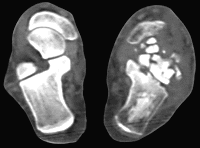

Перелом пяточной кости: КТ снимки и лечение